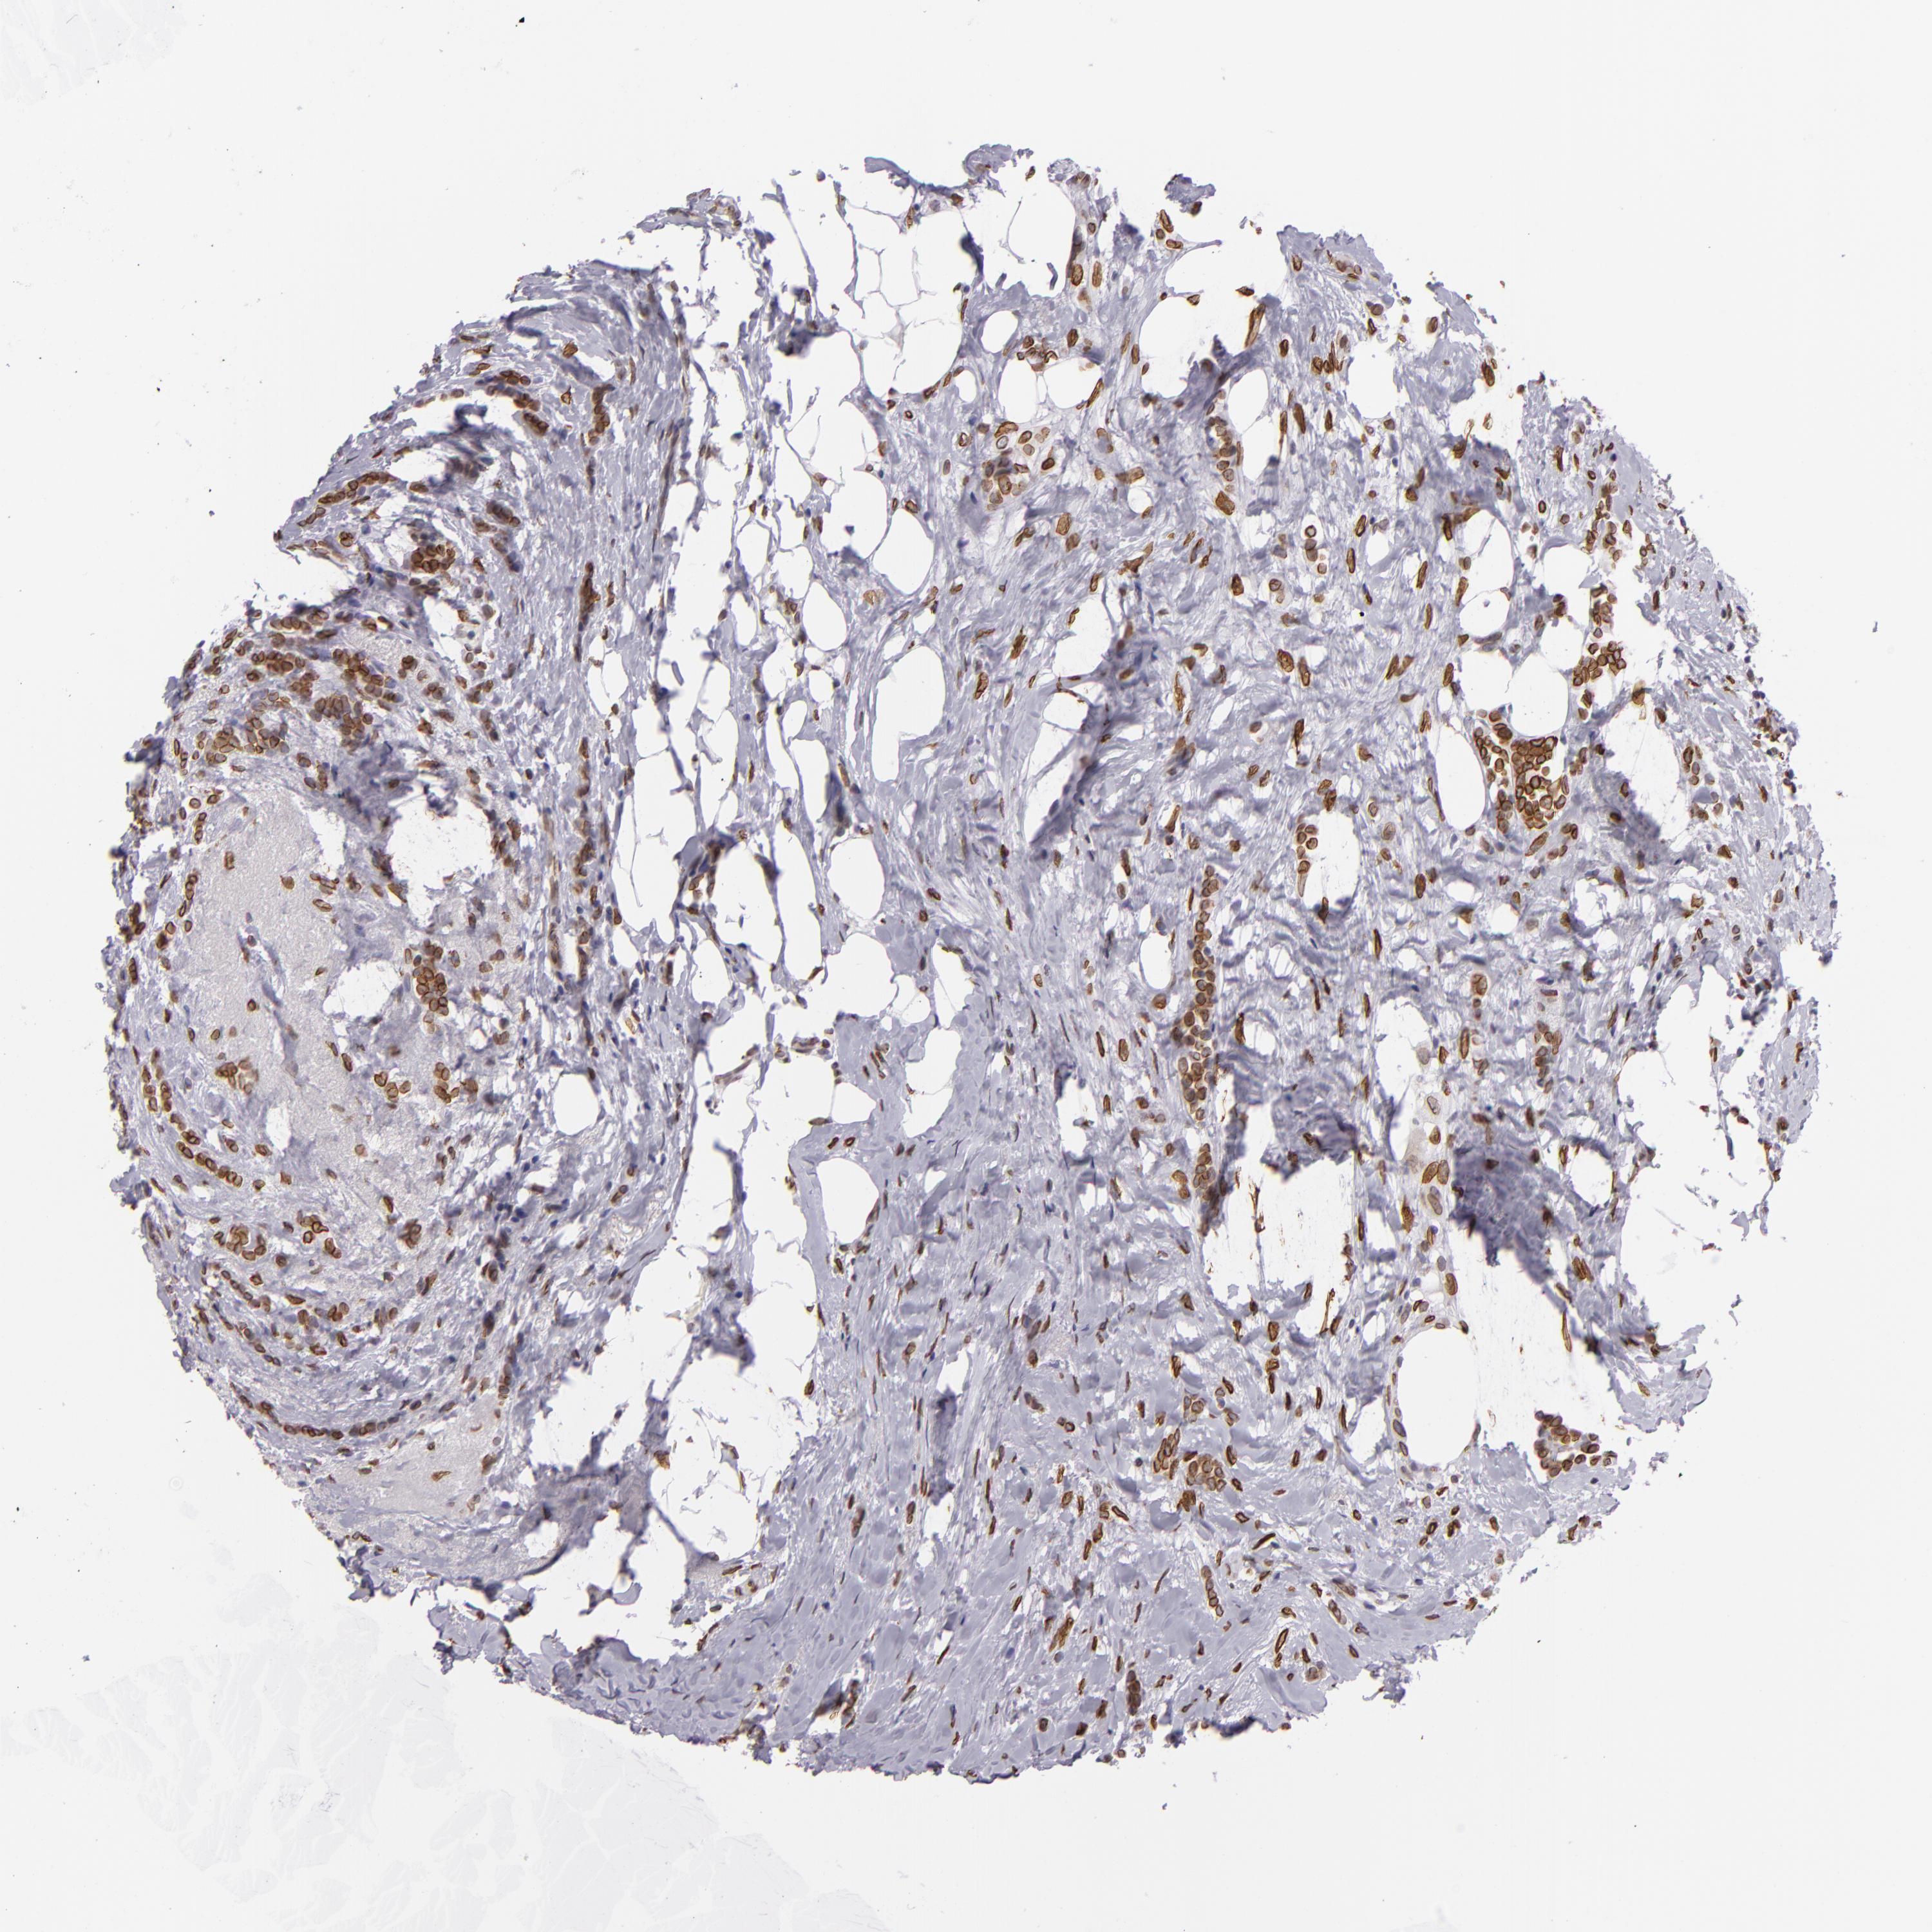

CANCER BREAST CANCER Show tissue menu

BRCA TCGA BRCA VALIDATION PROTEIN EXPRESSION